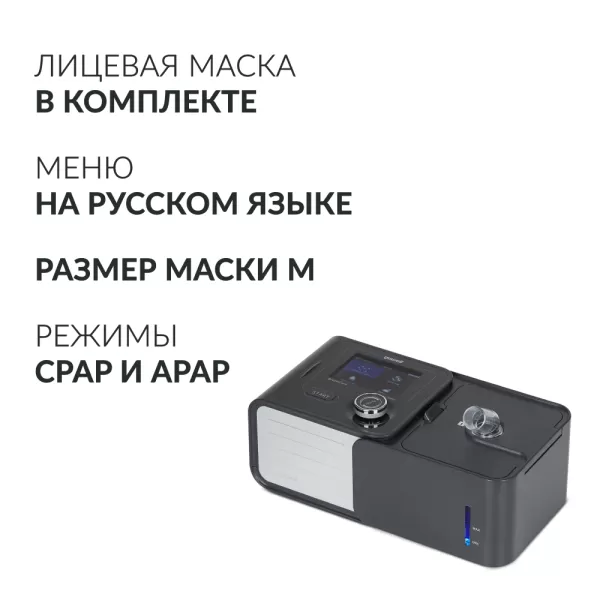

Аппарат дыхательной терапии апноэ СИПАП Yuwell YH-580

39 900 руб./шт

Под заказ

Наши менеджеры обязательно свяжутся с вами и уточнят условия заказа